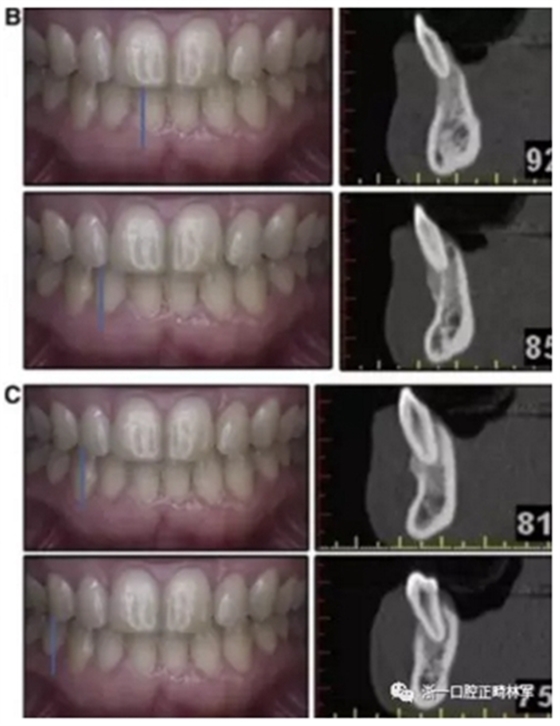

患者決定采用非手術(shù)治療方法,側(cè)貌沒(méi)有任何預(yù)期的變化。治療后面部照片(圖5)顯示她改善的微笑和側(cè)貌,包括尖牙保護(hù)合。由于先天性第一前磨牙缺失,右磨牙關(guān)系為III類。治療后牙齒石膏模型(圖6)顯示實(shí)體牙齒交錯(cuò)排列情況,并且全景X線片顯示可接受的牙根平行度而且沒(méi)有牙根吸收表現(xiàn)(圖7)。最終的頭影測(cè)量片(圖7)證實(shí)了面部評(píng)估,并且描跡圖顯示深覆蓋的改善,同時(shí)保持上頜切牙位置并通過(guò)測(cè)量ANB角度和Wits評(píng)估改善骨性II級(jí)關(guān)系(表)。治療前后的疊加圖顯示由于下頜切牙前傾的增加改善了下唇平衡(圖8)。如相關(guān)治療計(jì)劃所預(yù)測(cè)的那樣,B點(diǎn)出現(xiàn)。A進(jìn)行牙科錐形束計(jì)算機(jī)斷層掃描以記錄下頜前牙區(qū)的骨質(zhì)變化。如預(yù)期的那樣,由于治療導(dǎo)致該區(qū)域的骨量增加(圖9)。